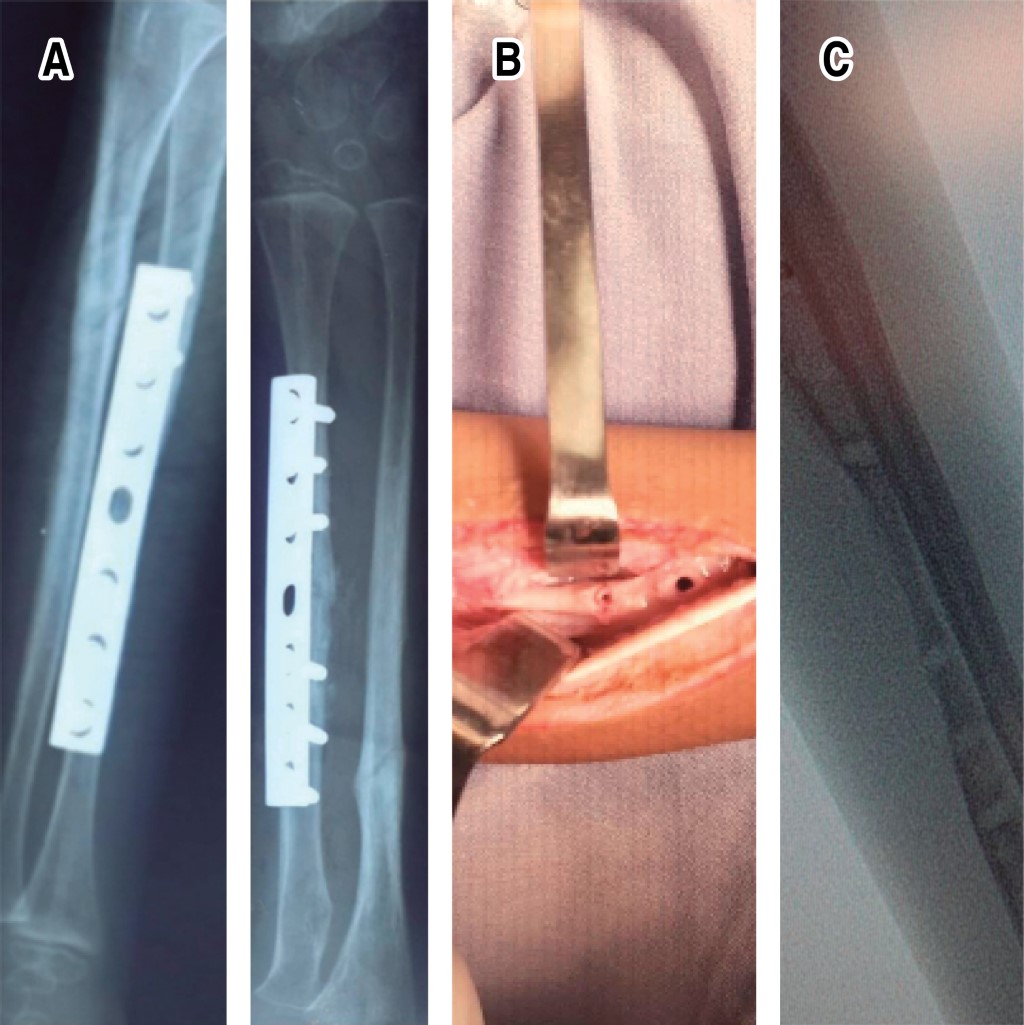

Introduction: the functions of vitamin D are very varied, from the regulation of cell proliferation, the modulation of the immune system, being the intestinal absorption of calcium, phosphorus, and magnesium one of the most important. Low levels of vitamin D are directly related to alterations in bone metabolism. Objective: to present the clinical case of a patient with a forearm fracture and vitamin D insufficiency, showing the complications that can occur in the bone consolidation process, as well as broadening the knowledge of this pathology. Clinical case: the case of a 7-year-old male patient is presented, who suffered a forearm fracture with a low-energy mechanism, evolving with delayed consolidation; there are important alterations of the bone structure after surgical management, when performing the endocrinological study, low levels of vitamin D are found, the bone changes are reversed when adequate levels of vitamin D are achieved. Conclusions: the clinical approach and surgical management in patients with fractures and suspected vitamin D disorders must be meticulous, given the potential complications that we may face.

Figure 2